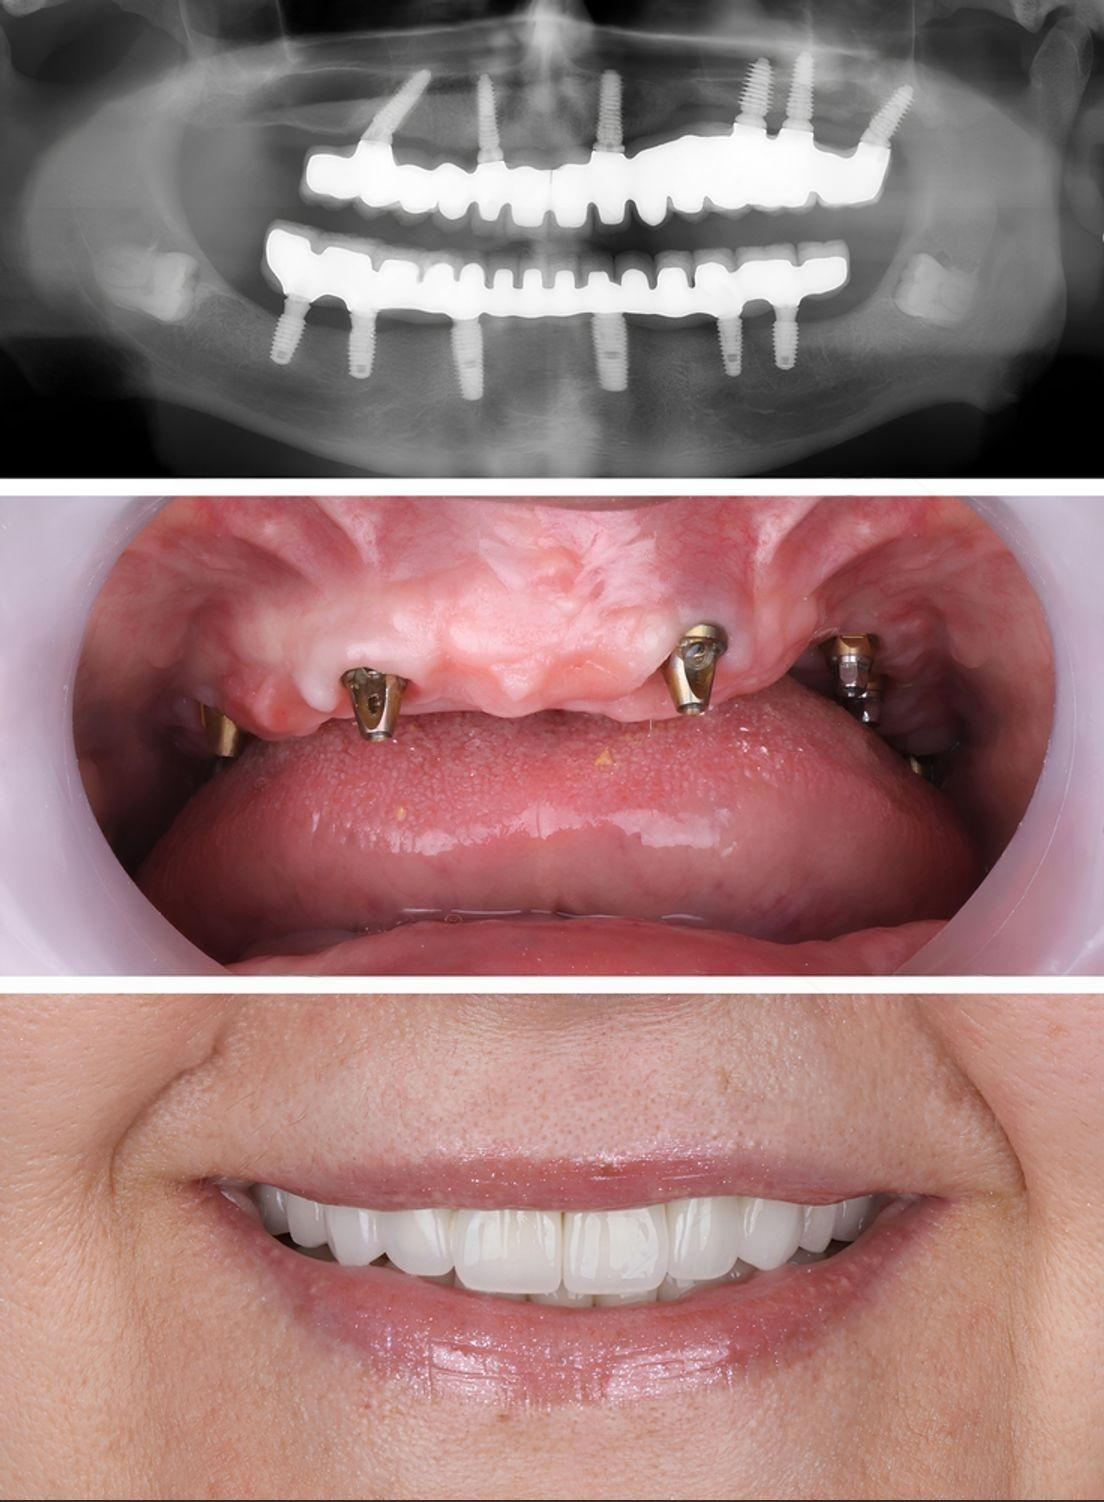

At Al Rayashi Dental Center, we believe that every smile tells a story — and we’re proud to be part of so many incredible journeys. Our Smile Transformations page showcases real patients who have trusted us to restore their confidence and enhance their dental health.

From subtle refinements to dramatic changes, these before-and-after cases highlight the power of expert care and advanced dental technology.